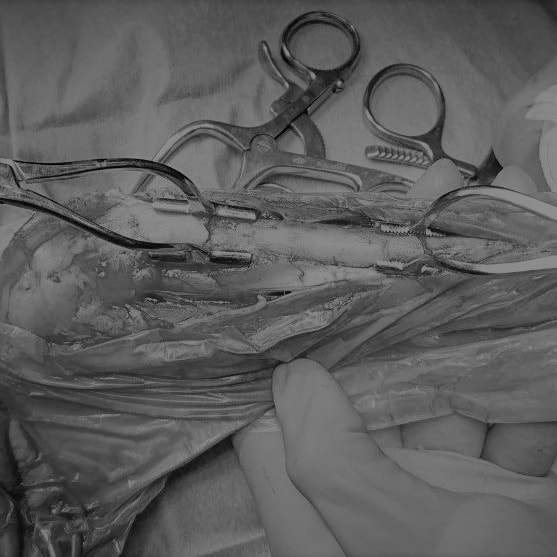

トイプードル 右遠位橈尺骨短斜骨折のALPSによる内固定

当院ではAdvanced Locking plate system(ALPS)と、Locking compression plate system(LCPS)という骨接合法で骨折症例の治療を行っています。

Advanced Locking Plate System

従来型のプレートのように広い面積で骨と接するプレートを用いて固定を行った場合、プレート下の骨はプレートとの接触面において血行が絶たれ壊死し、それがリモデリングされると骨密度が低下する。この骨密度の低下防ぐために、骨折部局所への血行を温存することの重要性が近年改めて認識されるようになってきている。Advaed Locking Plate System (ALPS)は従来型のプレートシステムの欠点を改良し、より使いやすく、より骨への血行を阻害しないようにというコンセプトで作られた。

Advanced Locking Plate System の特徴

- 骨への血行障害は最小限である

- 上下左右にベンディング可能でより3次元的な成形が可能

- すべての部位においてプレート強度は均一である

- ロッキングスクリューと圧着型スクリュー(皮質骨スクリュー)の双方が使用できる

- ダイナミックコンプレッション機能

- 生体親和性の高いチタン製

- トイ犬種から馬まで応用できるサイズ展開がある